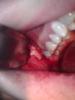

Zborzh Опубликовано 9 ноября, 2012 Поделиться Опубликовано 9 ноября, 2012 Удаление 2-х зубов,место действия районная поликлиника,время исполнения -50 мин. Ссылка на комментарий

АнтонТЛТ Опубликовано 9 ноября, 2012 Поделиться Опубликовано 9 ноября, 2012 По сколько узлов вяжете? Как-то кончики ниток кажутся короткими Ссылка на комментарий

Zborzh Опубликовано 9 ноября, 2012 Поделиться Опубликовано 9 ноября, 2012 3-1-2 Короче обрезал,чтоб не мешались . 1 Ссылка на комментарий